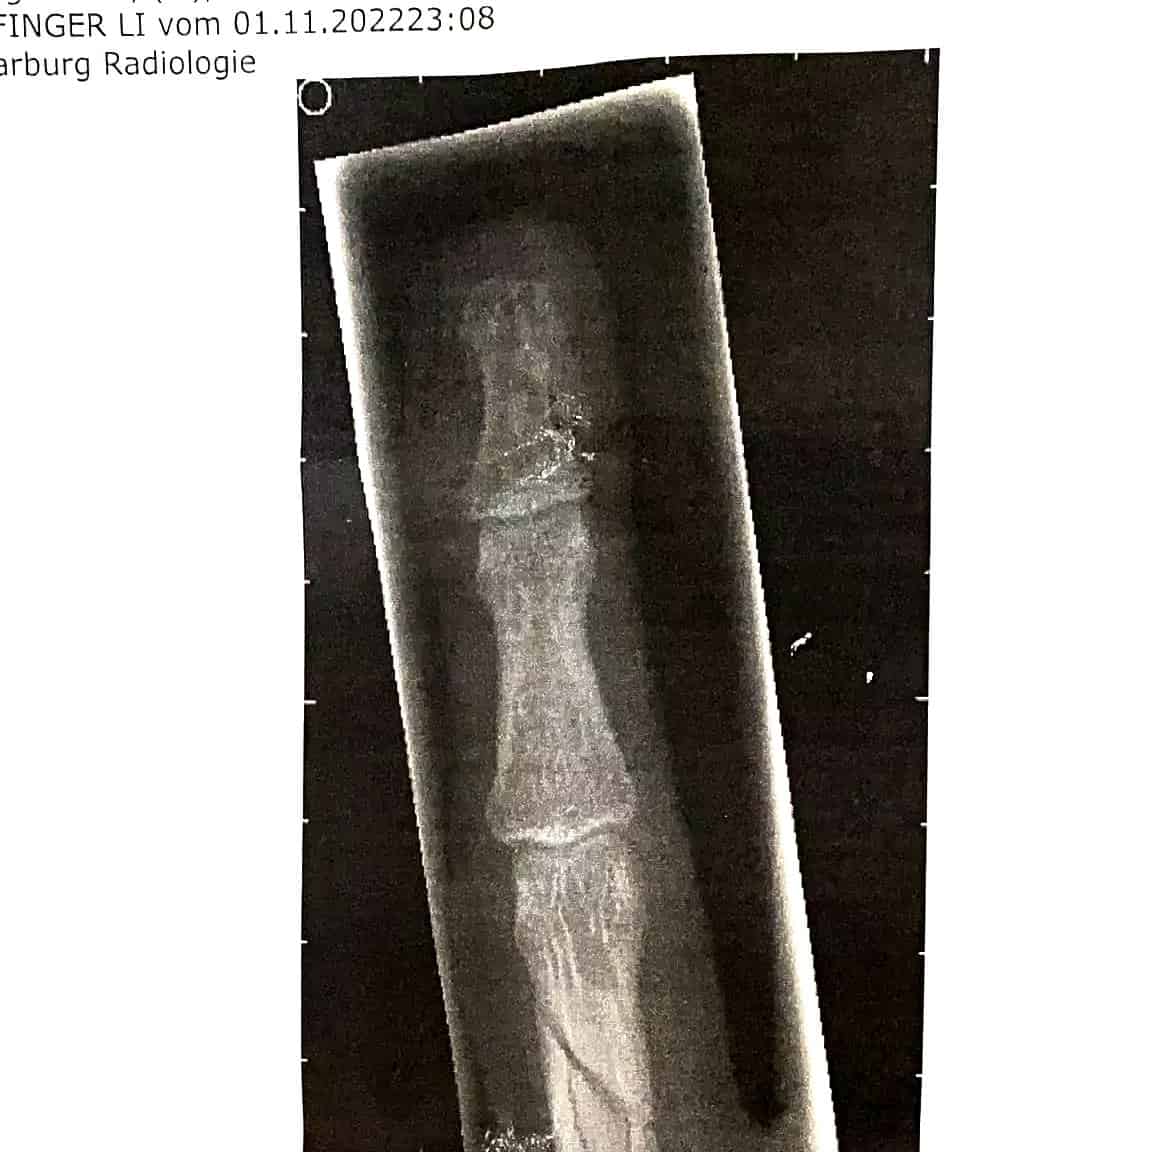

„Meine Hand ist gebrochen“ – eine Aussage, die faktisch nicht stimmt. Genau genommen ist ein Knochen meines Ringfingers gebrochen. Was wird hier sichtbar: Unsere Kommunikation und Sprache offenbart die Eingebundenheit konkreter Elemente in unterschiedliche Systeme.

Was bedeutet das? Der gebrochene Knochen ist eingebunden in das System des Skeletts, des Fingers, der Hand, des Menschen und viele mehr. Vor allem fällt die Eingebundenheit in diese Systeme auf, wenn das entsprechende Element nicht so funktioniert, wie es soll. Der Knochen ist gebrochen. Und das hat Auswirkungen auf alle Systeme, in die er eingebunden ist. Gerade in alltäglichen Situationen wird das offenbar: unter der Dusche, während des Essens etc.

Systeme sind konservativ. Das bedeutet, dass sie auf den Erhalt ausgerichtet sind. Konkret: ist ein Knochen gebrochen, fängt der Körper sofort an, alles dafür zu tun, den Ursprungszustand wieder herzustellen. Und das auf der Basis eines Bauplans, der in jeder Zelle, in der DNA gespeichert ist. Stimmt etwas nicht, konzentriert sich die Energie an entsprechender Baustelle. Die Wiederherstellungsmaßnahmen werden eingeleitet.

Mein Finger musste nach dem Bruch erst einmal gerichtet werden. Denn: Wenn die Bestandteile des Knochens nicht richtig aufeinander liegen, wird der Körper dennoch das Beste geben, um das zu reparieren, was zu reparieren ist. Warum? Um die bestmögliche Funktionalität schnellstmöglich wieder zu gewährleisten. Auch wenn der Knochen dann schief zusammenwächst. Das hat wiederum einschränkende Auswirkungen auf sämtliche Systeme und System-Ebenen.

Einen schief zusammen gewachsenen Knochen zu brechen tut weh – und es lohnt sich. Wichtig ist sich ein Umfeld zu suchen, in dem wirken. Natürlich wollen wir die besten Ärzte an unsere Knochen lassen. Sie wissen, was es temporär braucht, um die bestmögliche Funktionalität wieder herzustellen. Vielleicht braucht es eine Schraube, eine Platte oder einen Draht, der dann nach einiger Zeit wieder rauskommt. Vielleicht tut es einige Zeit weh, und dennoch eröffnet das Ergebnis neue Möglichkeiten.

Mein Knochen heilt gerade, das Richten tat gar nicht so weh, wie erwartet und die Operation war wirklich interessant. Aber das ist vielleicht auch “nur” ein persönlicher Fabel.